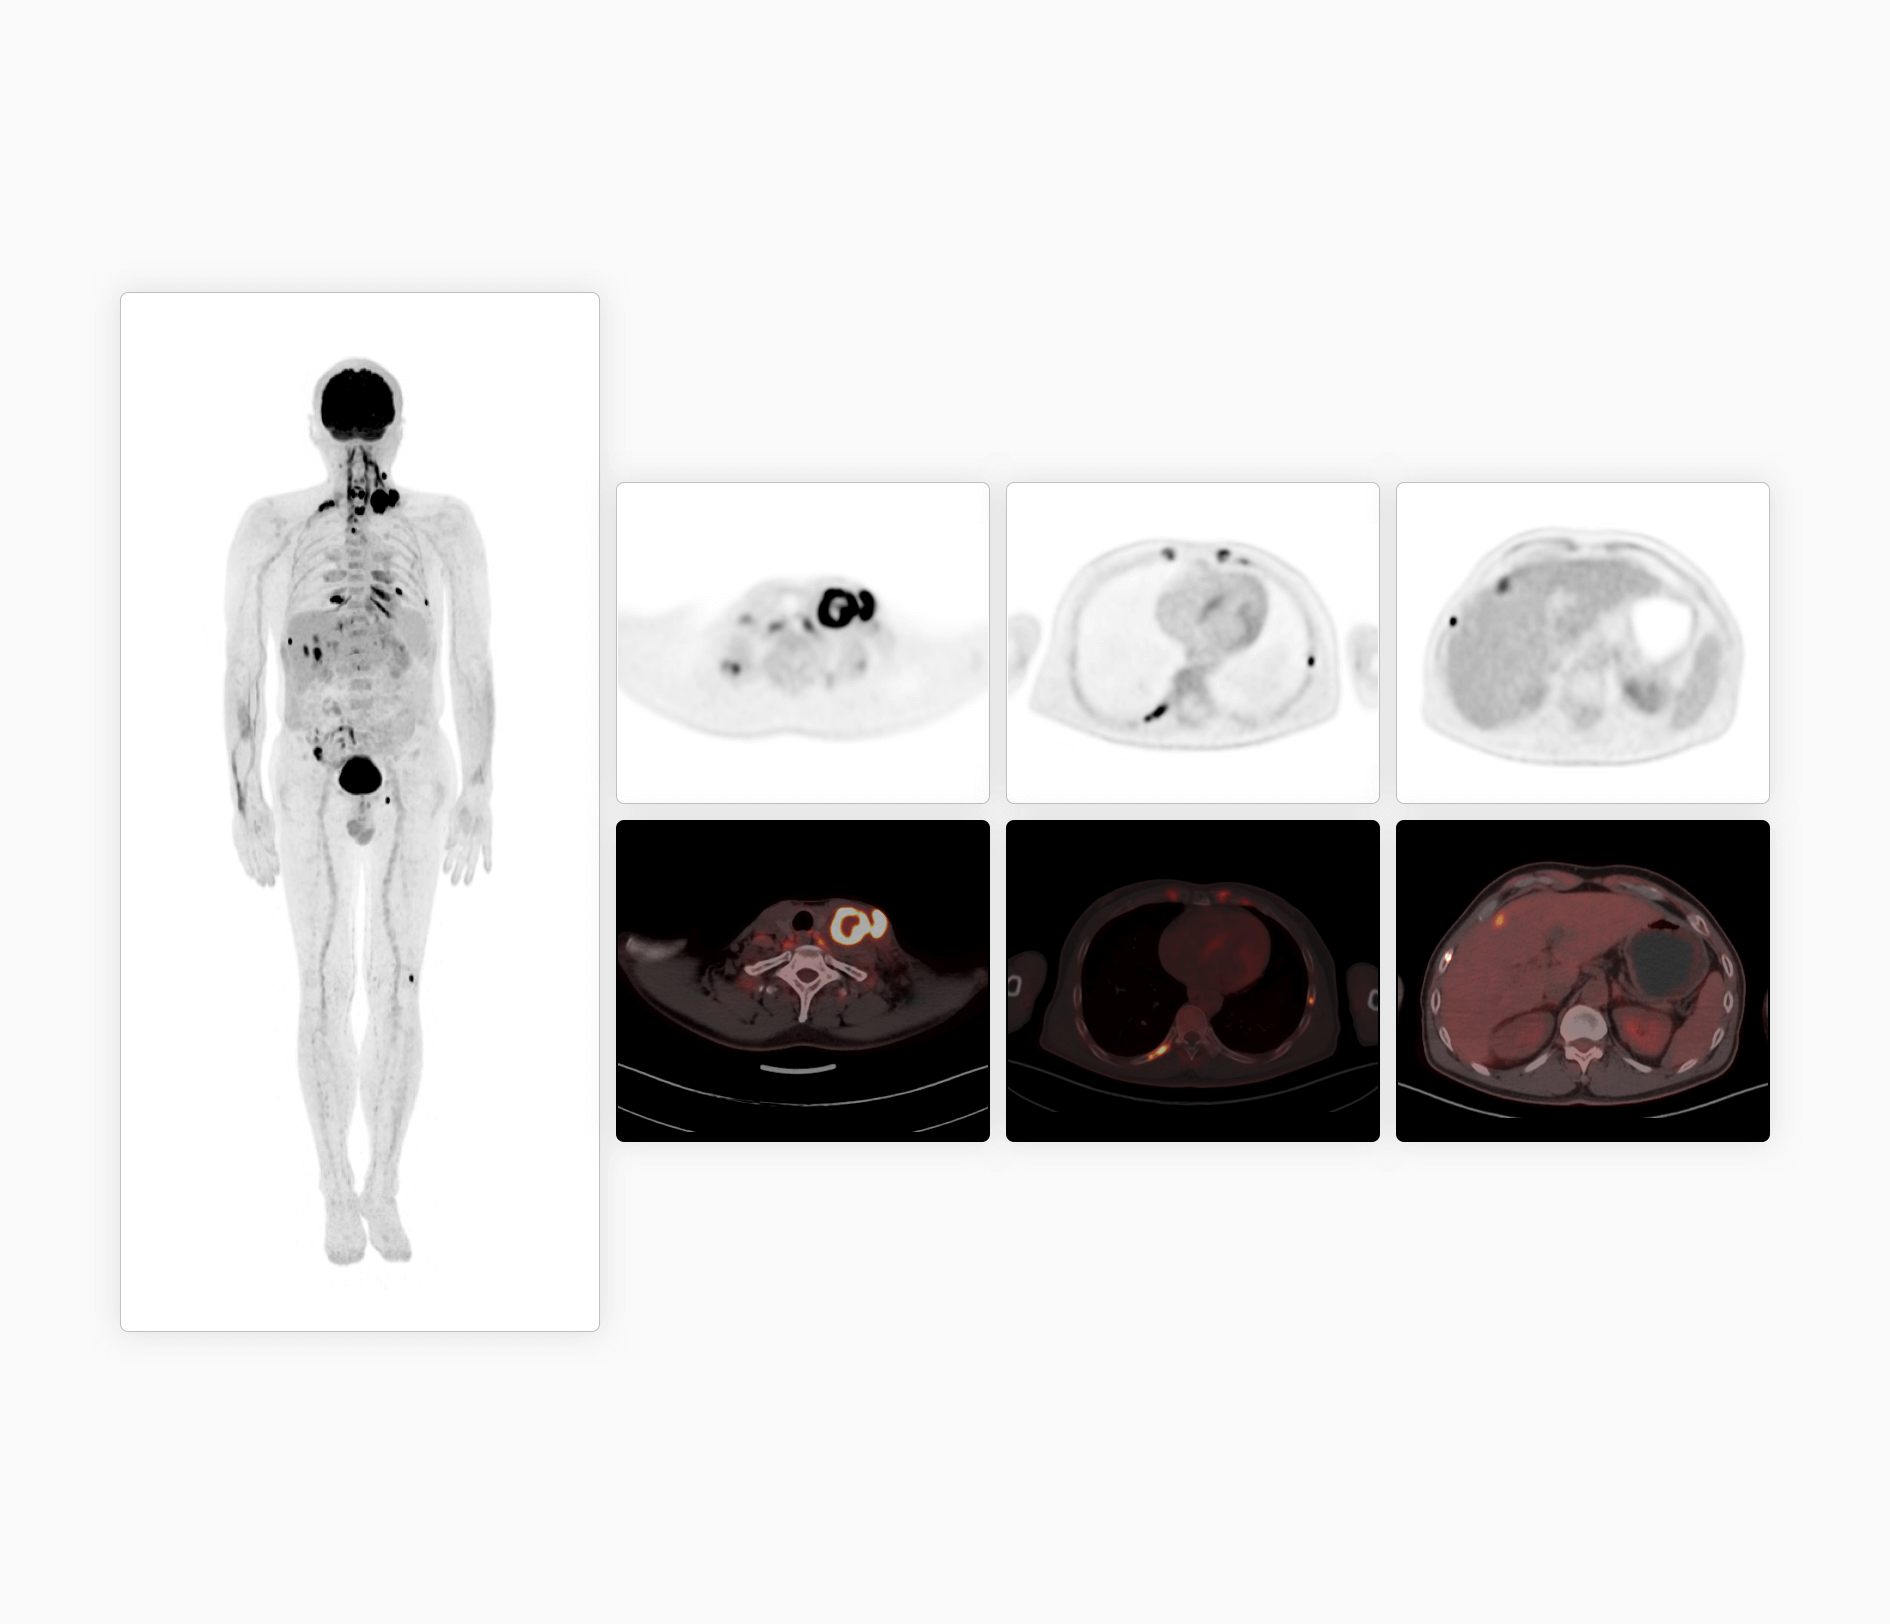

探索赋能

「类两米」高清精准影像

时空影像链数据源头提升CT图像质量

超高机架转速成就精准CT心脏扫描

从冠脉CTA到PET心肌灌注全套工作流

提供CT及PET全方位精准心脏功能评估*

源头提升脑部精细解剖结构显像

大幅提升脑部图像信噪比,微小结构精确显像

基于原始数据自动识别运动轨迹,有效消除头部运动伪影

提供全脑智能神经高级分析*,辅助临床精准诊断